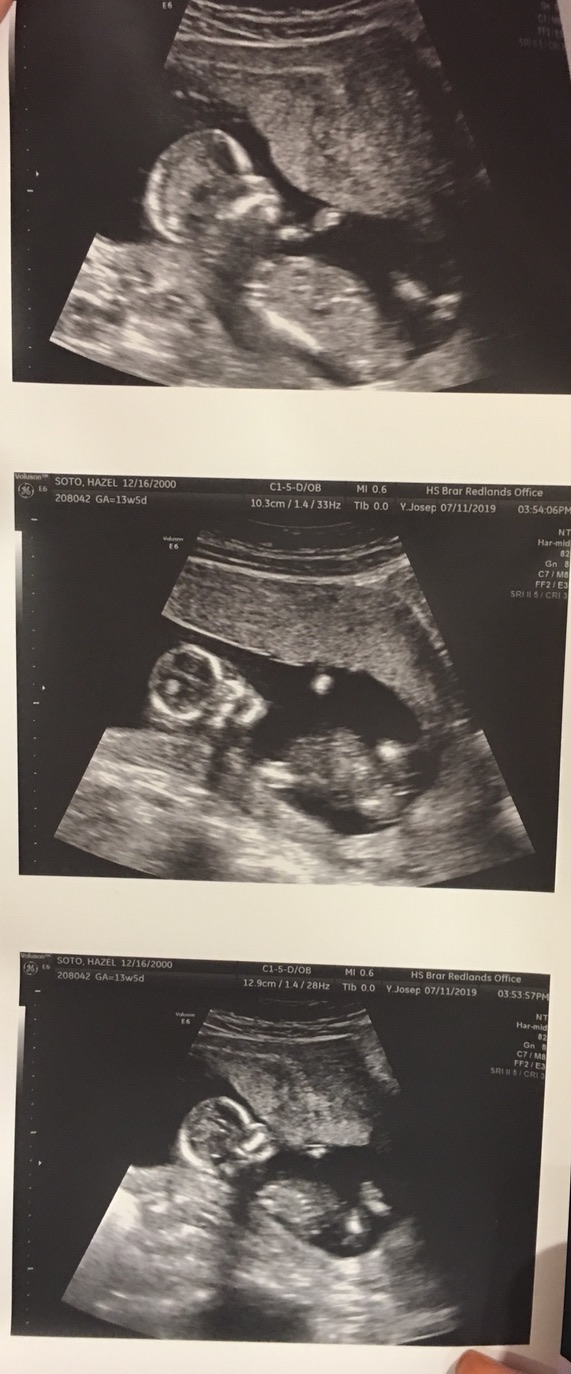

It’s been four months since and of course it has still been difficult but the support I have received from my family and my boyfriend is incredible. Despite coming from a religious, mexican family they still try to help me in whatever way they can. I was lucky enough to find a boy who helps, supports, and encourages in every way. This whole journey has really helped me appreciate the support I have in my life and appreciate the people in my life in a whole new perspective. I was truly blessed and I cannot be any more thankful for all of it.